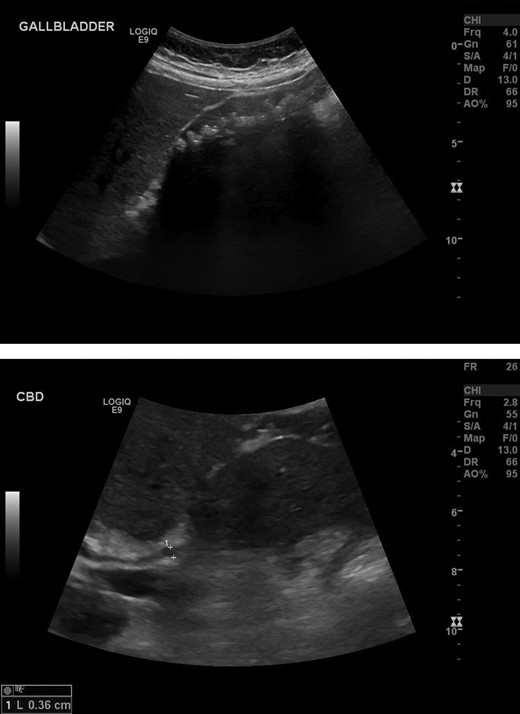

Bloods (see Fig. 1) were notable for an elevated amylase, gamma GT and alanaine aminotransferase. C-reactive protein was also elevated. Chest X-ray was normal and did not indicate any free air under the diaphragm. Ultrasound of the abdomen was performed and identified a gallbladder containing multiple small gallstones. There was no evidence of gallbladder wall thickening or intra/extra-hepatic bile duct dilatation (Fig. 2).

Extensive number of shadowing gallstones in the gallbladder. Negative for thickening of the anterior gallbladder wall. Negative for intra or extra-hepatic biliary dilatation.